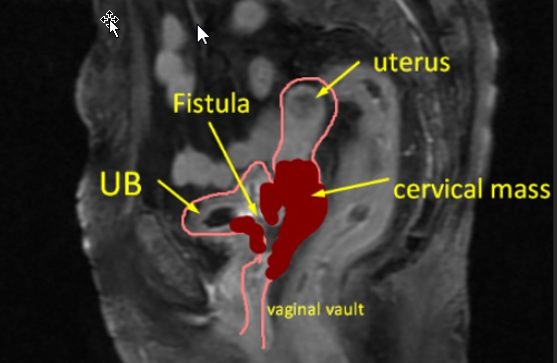

Visual Annotations & Clear Language

Receive annotated images with clear visual markers, a plain-language summary, and actionable insights for your next steps.

Annotated images + full written report

- Annotated scan images